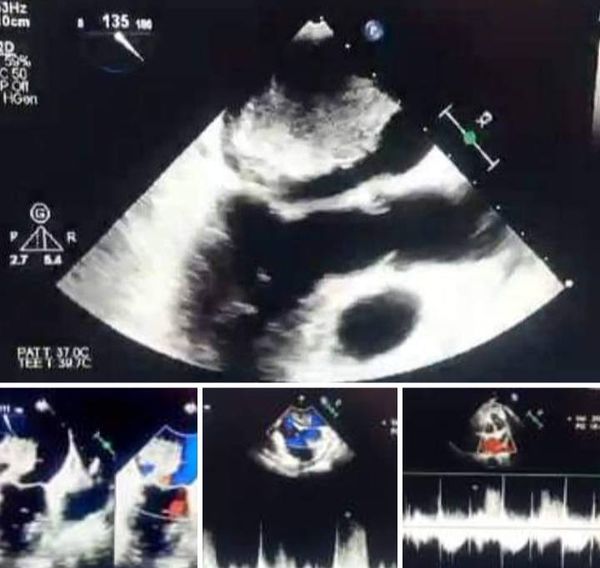

كان مستشفى القلب بجامعة أسيوط استقبل مريضة من محافظة المنيا تبلغ من العمر ٥٦ عاما، تعاني من ضيق في التنفس وثقل بالصدر منذ ٥ أعوام، ولم تشخص بالتشخيص صحيح، ليتم إجراء مناظرة للمريضة من قبل الدكتور علي تهامي مدرس أمراض القلب، وعقب توقيع الكشف الطبي والاشاعات تبين وجود ورم كبير الحجم بالأذين الأيسر من القلب، وعلى الفور قرر الفريق الطبي الذي تشكل من الدكتور محمد فاروق مدرس جراحة القلب والصدر، والدكتور عمر عرفات مدرس مساعد جراحة القلب والصدر، والدكتور محمد عماد مدرس مساعد جراحة القلب والصدر، والدكتور مصطفى لؤي و الدكتور أحمد وهبه نواب جراحة القلب والصدر، والدكتور أحمد مندور استشاري التخدير والرعاية المركزة، إجراء عملية قلب مفتوح لاستئصال الورم من داخل القلب، ليتم بعدها نقل المريضة للعناية المركزة، لتستقر حالتها بعد ذلك وتغادر المستشفى عقب إجراء الجراحة بأربعة أيام فقط.